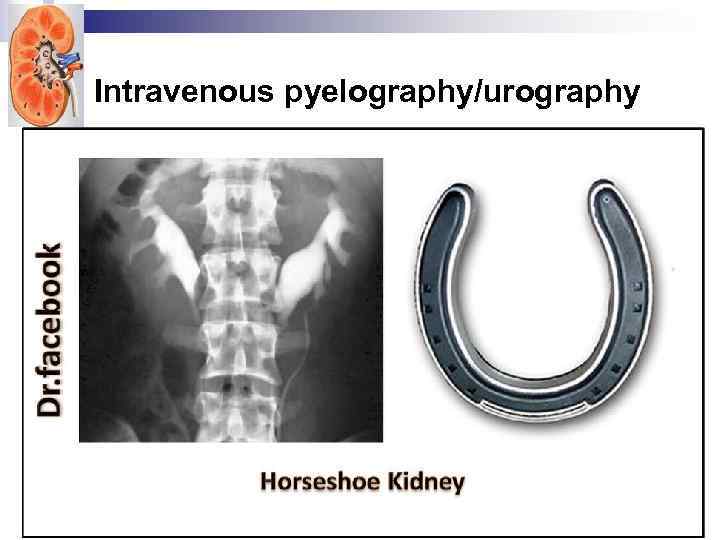

Intravenous pyelography/urography

Intravenous pyelography/urography